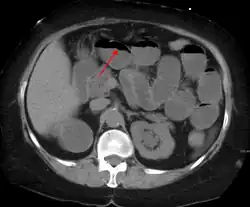

A small bowel obstruction as seen on CT

Causes of bowel obstruction include adhesions, hernias, volvulus, endometriosis, inflammatory bowel disease, appendicitis, tumors, diverticulitis, ischemic bowel, tuberculosis and intussusception.[1][2] Small bowel obstructions are most often due to adhesions and hernias while large bowel obstructions are most often due to tumors and volvulus.[1][2] The diagnosis may be made on plain X-rays; however, CT scan is more accurate.[1] Ultrasound or MRI may help in the diagnosis of children or pregnant women.[1]

The main diagnostic tools are blood tests, X-rays of the abdomen, CT scanning, and ultrasound. If a mass is identified, biopsy may determine the nature of the mass.

Radiological signs of bowel obstruction include bowel distension (small bowel loops dilated >3 cm) and the presence of multiple (more than 2) air-fluid levels on supine and erect abdominal radiographs.[16] Ultrasounds may be as useful as CT scanning to make the diagnosis.[17]